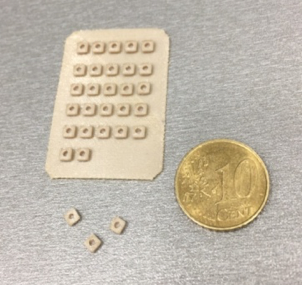

V roku 2017 boli takisto pripravené testovacie vzorky pre testy biokompatibility a viability buniek, ktoré boli v tomto roku aj zrealizované.

Obr. 4 Aditívne vyrobené vzorky z materiálu PEEK určené na laboratorne testovanie na humánnom bunkovom modeli v in vitro podmienkach